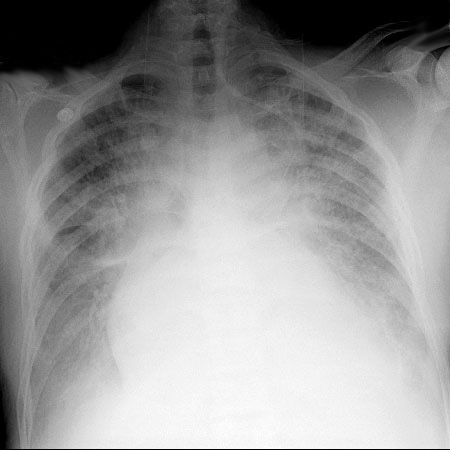

CXR for case found here:

(CXR source: https://www.med-ed.virginia.edu/courses/rad/cxr/postquestions/posttest.html)